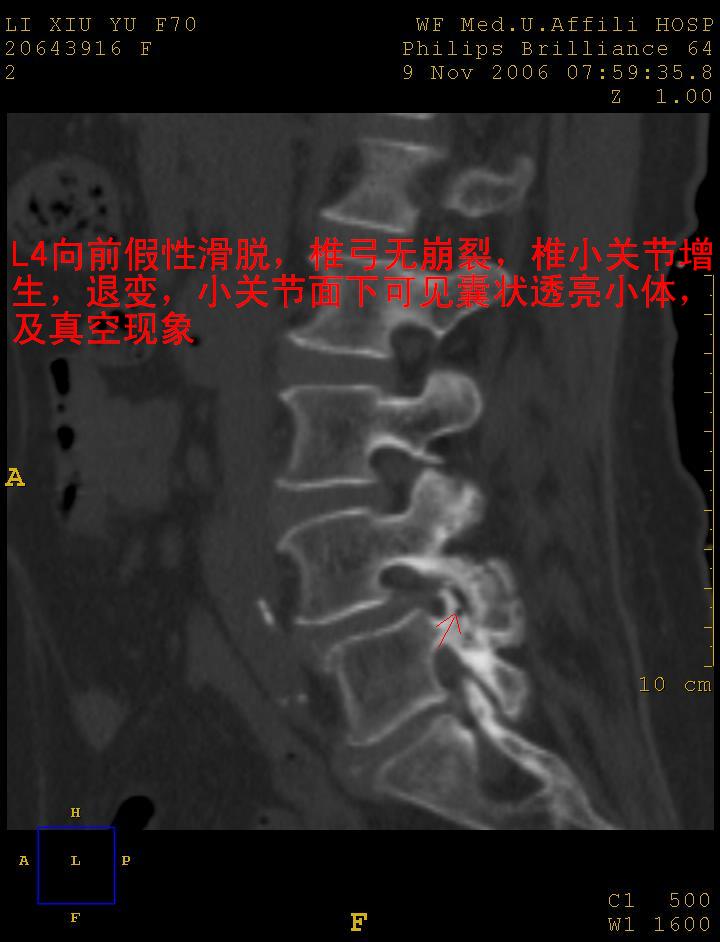

考虑:1、腰4假性前滑脱(1度,小关节退行性性骨关节病所致);

2、腰5--骶1椎间盘退行性变。

1:l4向前滑脱,l4-5小关节退性变。没有峡部裂。

1腰椎骨质增生,2l4向前滑脱(假性,矢状位椎弓峡部连续),3腰5-骶一椎间盘退变,4小关节面综合征

1 腰4椎弓崩裂,腰4椎体向前ι度滑脱并椎小关节交锁,腰4/5小关节明显增生硬化,间隙内可见真空征。

2 腰椎间盘不同程度膨出,腰4/5、腰5/骶1椎间盘突出,腰4/5椎间隙变窄,腰5/骶1间盘变性(间隙内可见真空征)。

诊断:腰椎退行性骨关节病。